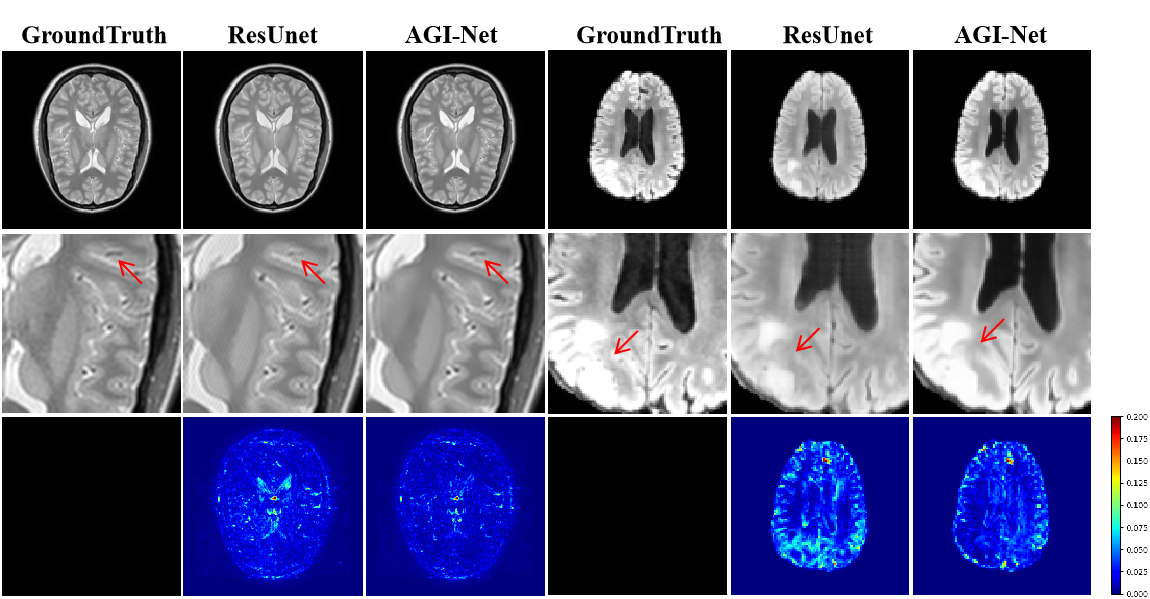

Refer to caption

Figure 5: Displays the (T1, T2)->PD synthesis results of pixel2pixel using the IXI dataset. The first row presents the ground truth along with the synthesis results from ResUnet and AGI-Net. The second row shows an enlarged view of the region of interest (ROI), while the third row illustrates the synthesis error map.

To better illustrate the synthesis performance of our method, we visualize the error maps and regions of interest (ROIs). The experiments were conducted on the IXI test set using a pixel-to-pixel framework. As demonstrated in Fig. 5, the synthesis results of AGI-Net show greater structural consistency with the ground truth compared to ResUnet, proving the superior adaptability of our method in capturing and fusing misaligned features across multiple modalities. Fig. 6 presents a comparative analysis of PCA feature maps across different feature stages of ResUnet and AGI-Net. The results clearly indicate that AGI-Net demonstrates superior noise resilience and captures more detailed structural information.